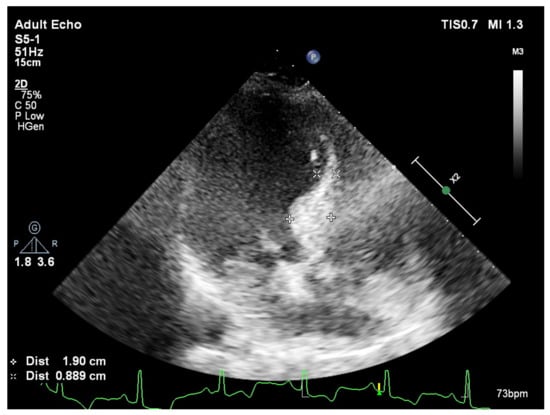

2. Basal Septal Hypertrophy and Clinic Observations

4. Heart Failure with Preserved Ejection Fraction

6. Cardiovascular Outcomes of Patients with HFPEP Who Are on Effective Antihypertensive Treatment